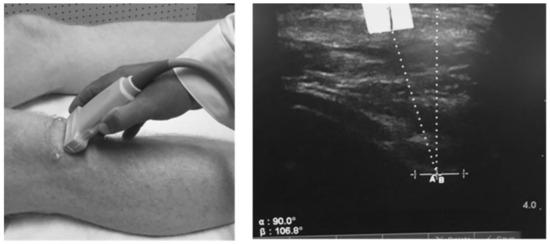

2.4. Static Patella Position

- Anillo, R.; Villanueva, E.; León, D.; Pena, A. Ultrasound diagnosis for preventing knee injuries in Cuban high-performance athletes. MEDICC Rev. 2009, 11, 21–28. [Google Scholar] [PubMed]